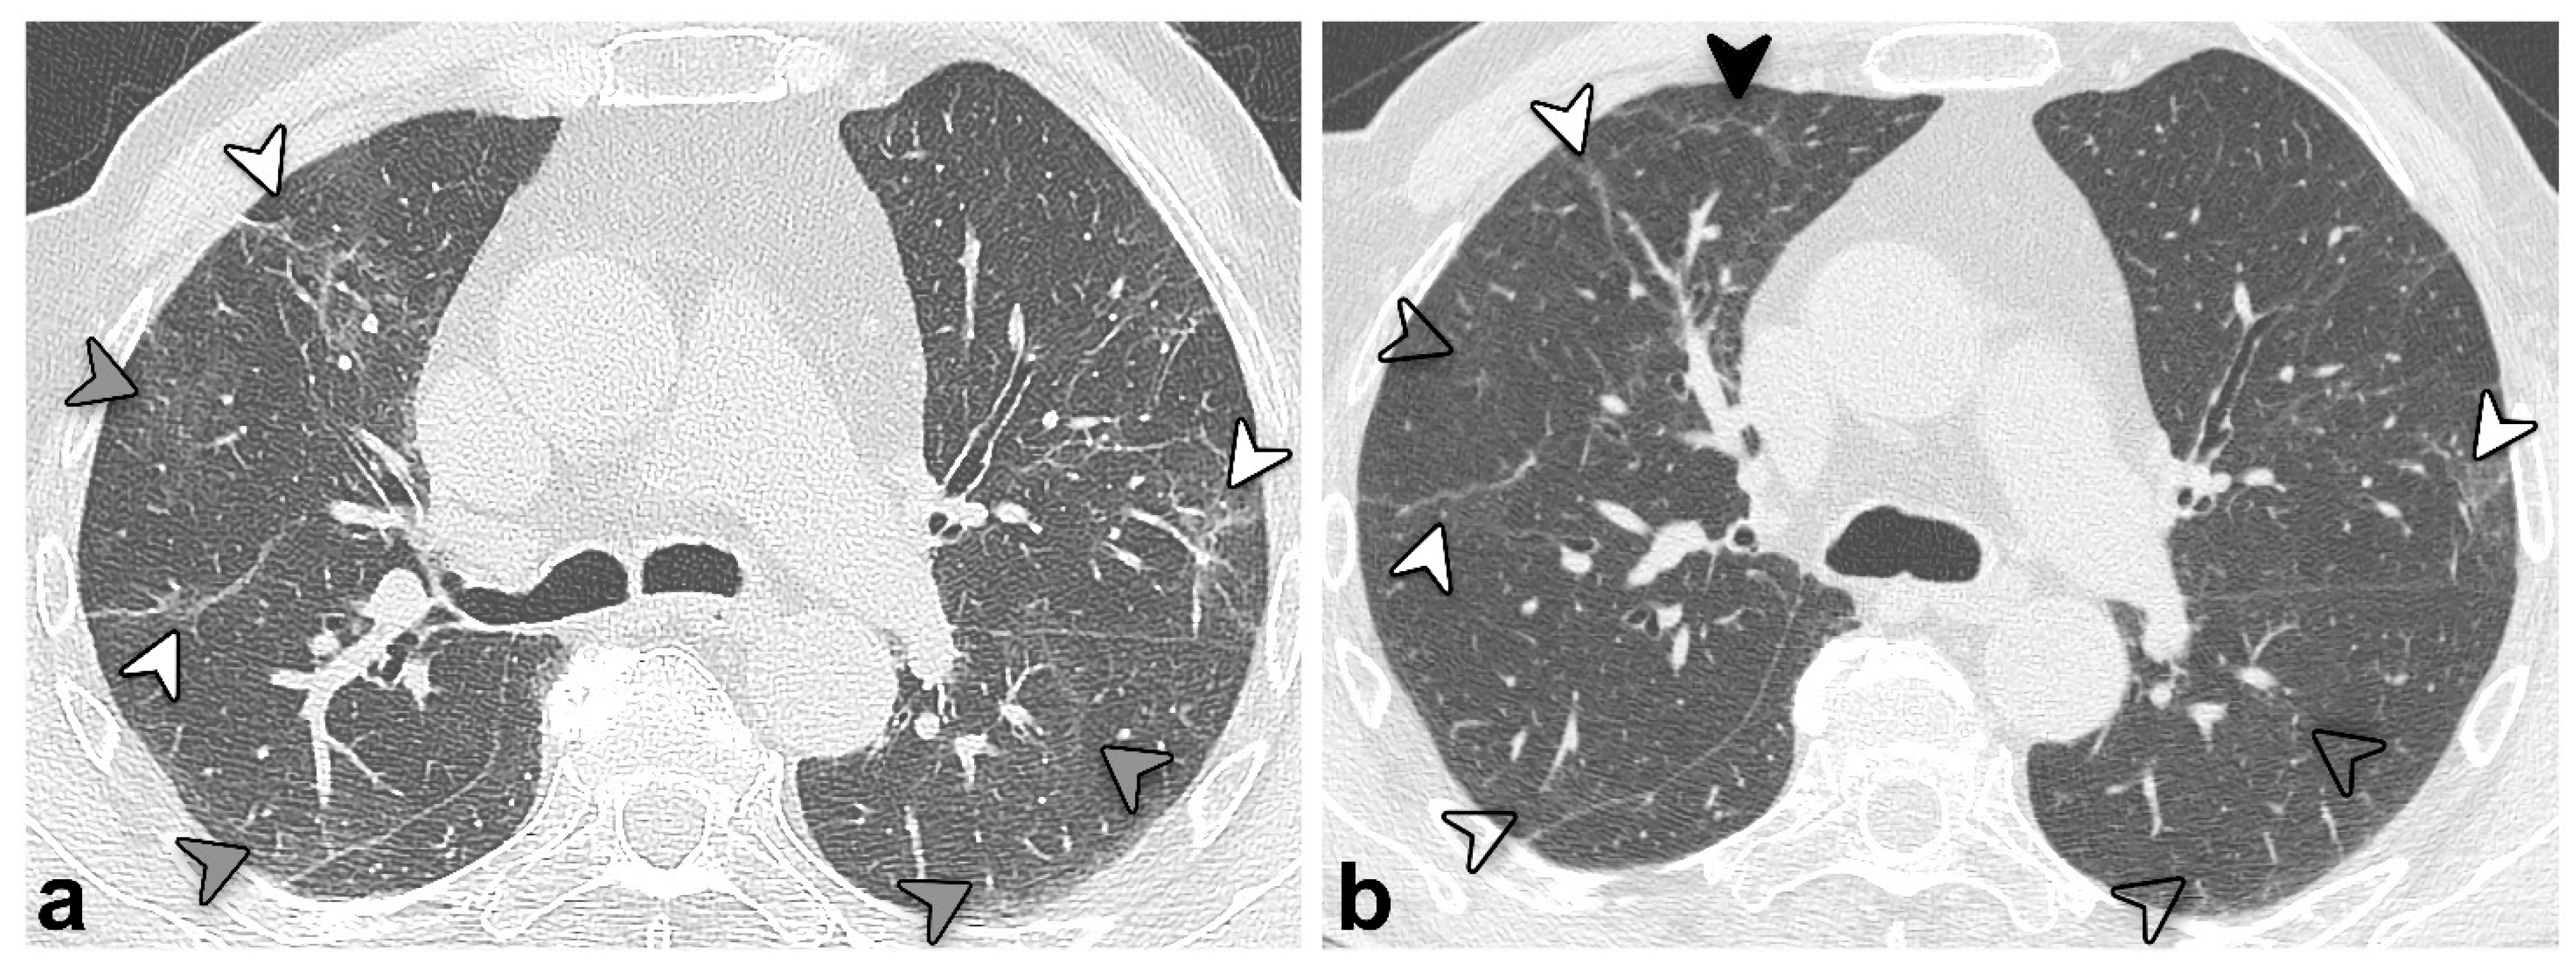

| Type of CT pattern | 0.038 | ||

| GGO | 8 (16) | 2 (4) | |

| Reticular | 31 (63) | 38 (79) | |

| Combined | 10 (21) | 8 (17) | |

| Consolidation | 2 (4) | 2 (4) | 1.000 |

| Architectural distortion | 45 (92) | 46 (96) | 1.000 |

| Bronchial dilatation | 44 (90) | 42 (88) | 0.683 |

| Distribution | |||

| Bilateral | 47 (96) | 48 (100) | NA ** |

| Axial distribution (central/peripheral/neither) | 1 (2)/18 (37)/30 (61) | 0 (0)/28 (58)/20 (42) | NA ** |

| Cranio-caudal distribution (superior/medium/inferior/none) | 2 (4)/1 (2)/7 (14)/39 (80) | 1 (2)/6 (13)/12 (25)/29 (60) | 0.047 |